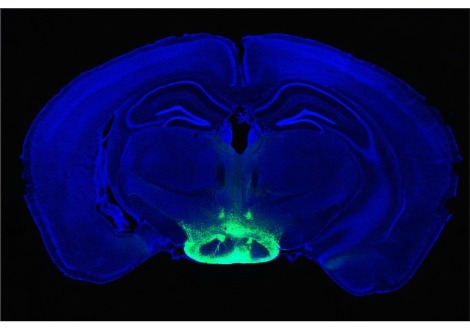

في مرض الزهايمر ، يمكن أن يتعطل الحاجز الدموي الدماغي بسبب تراكم بروتين الأميلويد ، خاصة عند الأشخاص الذين يحملون متغيرًا جينيًا يسمى APOE4. يُظهر هذا العرض ثلاثي الأبعاد للأوعية الدموية المهندسة الحاملة لـ APOE4 تراكمًا كثيفًا لبروتين الأميلويد (الأخضر).